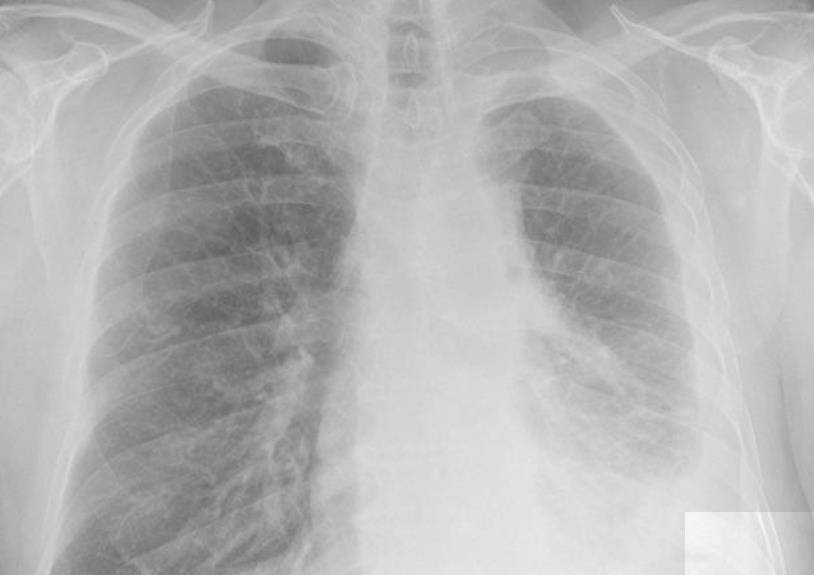

导语:很多人都觉得上呼吸道感染无所谓 , 但实际上当上呼吸道感染病不注意的时候 , 很有可能会导致病原体进入肺部当中 , 进而导致相应的肺炎 , 而肺炎随着时间进展 , 很有可能会诱发肺组织化脓性病变 , 早期称为化脓性肺炎 , 随着时间的推移很有可能会诱发肺脓肿等相应疾病 。

01临床上根据感染的来源进行了相应的分类 , 实际上并非仅仅吸入才能导致肺脓肿

吸入性肺脓肿是临床上面较为常见的一种肺脓肿主要病因 , 它主要是因为病毒经过口呼吸道等相应物质进入到肺部 。 正常的生理情况下 , 病原体被人体吸入过程中 , 会有效地被支气管当中的纤毛以及咳嗽甚至细胞免疫等相应免疫系统快速清除 。

但当出现意识障碍 , 比如醉酒、麻醉、心血管疾病等相应问题 , 或者因为极度疲劳等原因导致身体免疫力和气道防御力急速下降的时候 , 吸入相应的病原体就很有可能会发生疾病 。

要注意的是除此以外 , 由于鼻窦炎和牙龈脓肿 , 等相应疾病很有可能会因为身体当中本身就存在大量的病菌竟然很容易会使得脓性分泌物被有效吸入致肺部诱发肺脓肿的产生通常情况下脓肿多为单侧发病 。 其发病部位主要和支气管解剖后以及具体吸入时的体位有关系 , 而正常情况下 , 右侧支气管较为狭窄 , 并且较为陡峭所以疾病好发于右侧 。

同时对该种致病菌进行相应的分离 , 能得到相应的感染源 , 其中较为常见的是个雷厌氧菌 , 而厌氧菌当中最常分离出来的是拟杆菌属以及消化链球菌属除此以外 , 少部分需氧菌和兼性运氧菌也可以导致该病的发生 , 比如肺炎球菌以及溶血性链球菌 。

2、继发性脓肿

实际上除了因为吸入所导致的感染以外 , 某些细菌性肺炎也有可能会导致肺脓肿的发生 , 这是因为肺部已经发生了相应的感染 , 但是没有得到良好的治疗 , 将可能会导致该病的发生 。 尤其是出现金黄色葡萄球菌等相应肺炎的产生就很有可能会导致肺脓肿 , 需要格外注意 。

除此以外 , 如果出现支气管扩张症、支气管囊肿、支气管肺癌、肺结核空洞等相应问题的形成会使得支气管的清洁功能发生相应的下降 , 进而导致大量的病菌更容易进入到体内 。

而当出现肺部周围疾病发生相应的脓肿的时候有可能会导致病菌在体内发生相应的转移导致肺部脓肿的产生 , 所以对于相应的膈下脓肿甚至肾脓肿几种脓肿等相应问题 , 很有可能会诱发肺脓肿 , 需要格外注意 , 同时一种称之为阿米巴的寄生虫 , 虽然主要好发于肝脏当中 , 但是如果肝脏出现破裂的问题 , 就很有可能会导致阿米巴肺脓肿 。

3、血源性肺脓肿

血源性肺脓肿多半是因为皮肤外伤所导致的化 , 等脓毒血症的产生 , 需要注意的是血源性肺脓肿一般出现在脓毒血症较为晚期的阶段 , 此时很有可能已经出现了相应的心肌损伤 , 严重者甚至可能会出现脑损伤等问题需要格外注意 。